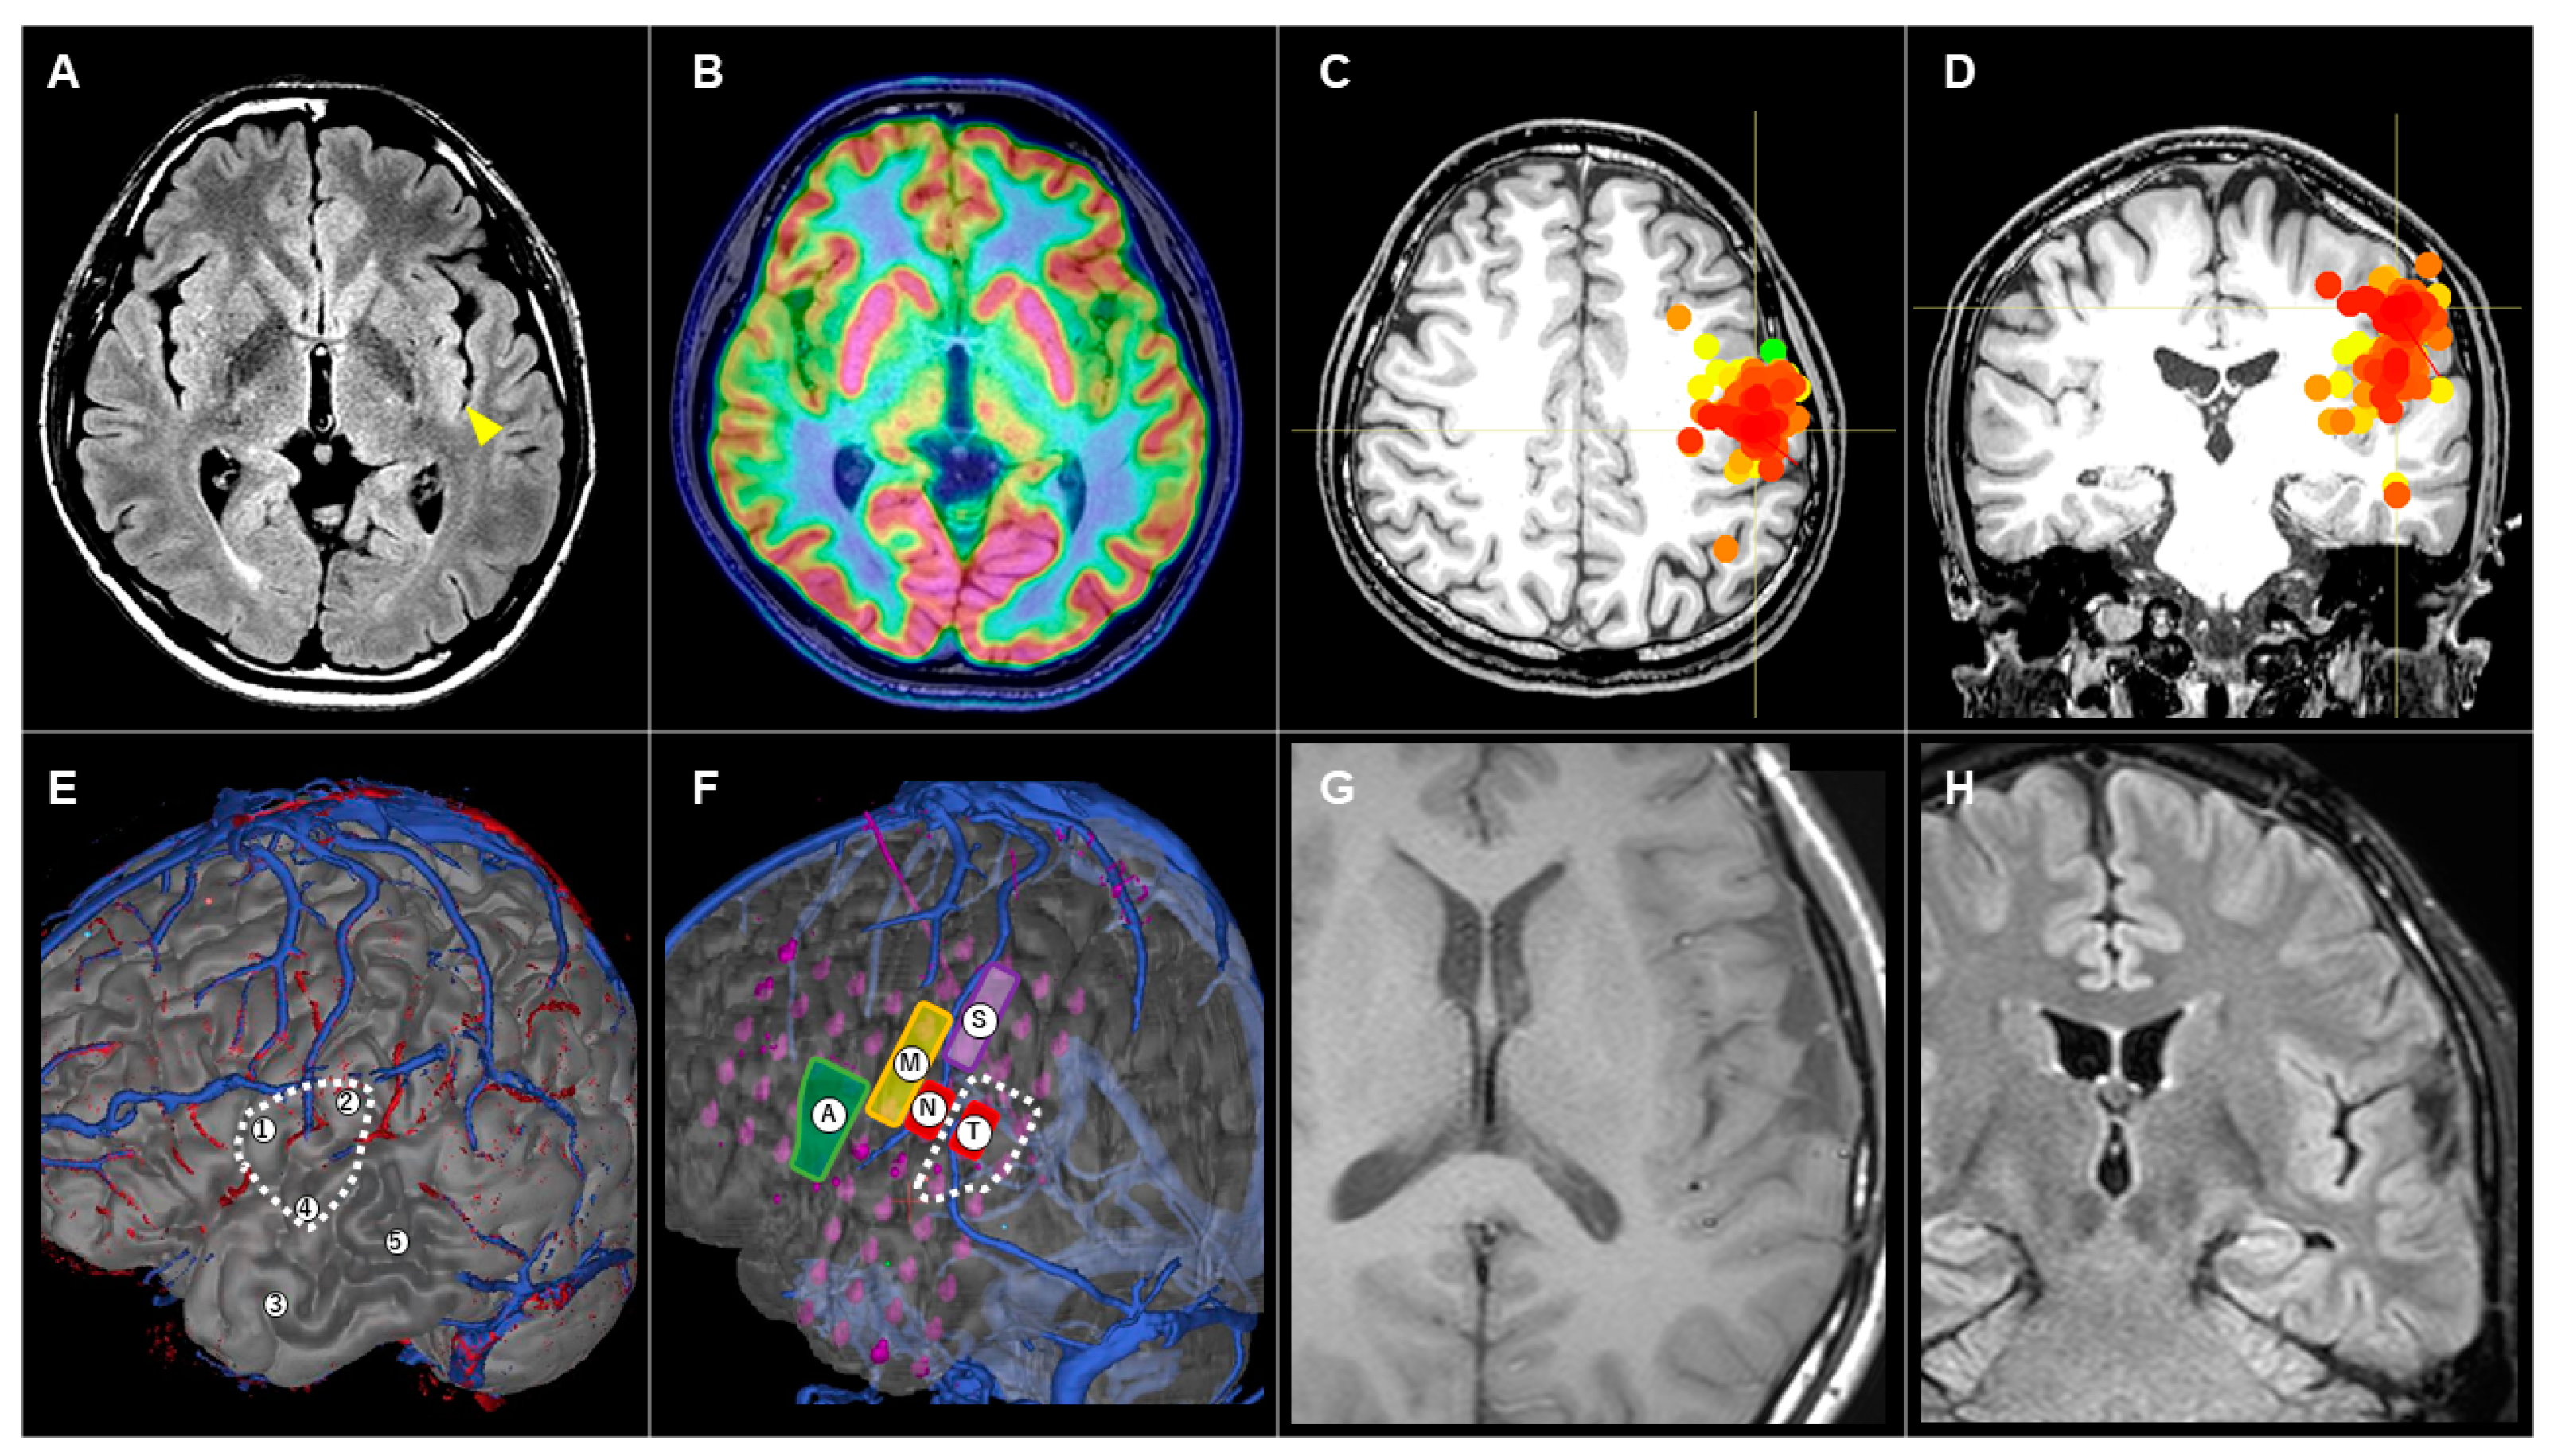

3.3.3. Patient #10 (AWC#3) (Figure 4)